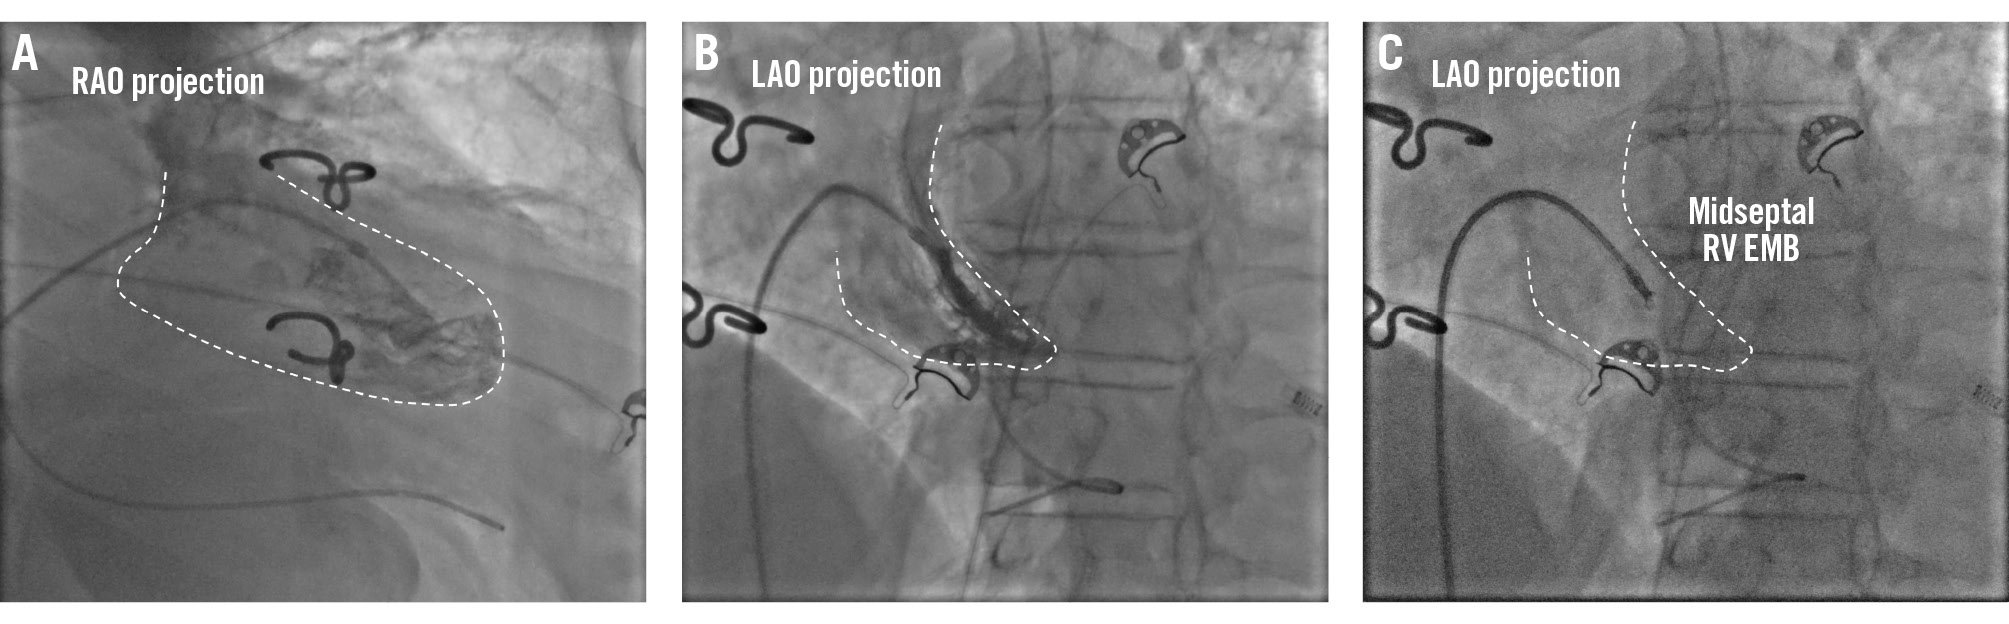

RV EMB is performed via the jugular, femoral, or brachial veins. For RV EMB sampling, the administration of heparin is not mandatory. In cases of an enlarged right atrium or an unfavourable angle for right ventricular access via the femoral vein, switching to jugular access or using steerable guiding catheters should be considered to facilitate the procedure. For RV EMB, the RV is reached through the tricuspid valve using the posteroanterior and the RAO projections, which is typically set at 30°. The RAO view provides a clear view of the right ventricular outflow tract and the right ventricular free wall to determine the mid-RV, apical, or RV outflow tract position, but the LAO 40° projection is most commonly used to guide tissue sampling from the ventricular septum (Figure 4). This projection provides a profile view of the interventricular septum (Figure 4), which is the preferred site for RV EMB to minimise the risk of injury to tricuspid valve apparatus and to the RV free wall with subsequent perforation. However, due to significant interindividual variability in cardiac long-axis orientation, it is important to adapt the fluoroscopy projections for each patient. Avoiding biopsy samples too close to the outflow tract is important as the procedure can damage the right bundle branch. In patients with left bundle branch block (LBBB), a temporary pacemaker should be considered or kept readily available because of the risk of complete atrioventricular (AV) block. An RV angiogram can be performed to identify the septum, and also transthoracic or intracardiac echocardiography can confirm bioptome positioning across the RV septum. Moreover, if a computed tomography scan is available, patient-specific computed tomographic fluoroscopic projections can be predicted20.

Figure 4. Right ventricular EMB. Example of a right ventricular endomyocardial biopsy. A) Fluoroscopic right anterior oblique (RAO) projection of a long sheath positioned in the mid-right ventricle over a pigtail catheter. B) Fluoroscopic left anterior oblique (LAO) projection of a long sheath in the right ventricle over a pigtail catheter and the long sheath pointing towards the right ventricular septum. These two complementary views facilitate the identification of the tissue sample site. C) Fluoroscopic views of the endomyocardial biopsy procedure in the mid-right ventricular septum. EMB: endomyocardial biopsy; RV: right ventricular